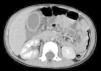

Se ingresa para analgesia, manteniéndose en dieta absoluta e iniciando tratamiento antibiótico por vía intravenosa con gentamicina, amoxicilina-ácido clavulánico y metronidazol. A las 12 h del ingreso, persiste dolor a la palpación abdominal, aunque de menor intensidad, sin vómitos ni alteraciones deposicionales. Se realiza control analítico, objetivándose aumento de la PCR a 218mg/l, y control ecográfico, donde persisten signos inflamatorios en el área vesicular, y grasa adyacente, mínima cantidad de líquido de aspecto inflamatorio y mínimo plastrón en asas próximas. Se solicita una tomografía computarizada abdominal urgente (fig. 2), en la que se reafirma el diagnóstico de CAA.

Debido a la persistencia de la clínica a pesar del tratamiento antibiótico y analgésico, el aumento de los reactantes de fase aguda y los hallazgos en las pruebas de imágenes con sospecha de gangrena de la vesícula biliar, se decide el traslado del paciente al servicio de cirugía pediátrica de referencia en la comunidad donde se procede a su abordaje quirúrgico confirmándose el diagnóstico de colecistitis aguda gangrenosa.

La asociación de manifestaciones clínicas poco evidentes, junto con la poca incidencia de esta afección, conlleva en muchas ocasiones un retraso en el diagnóstico. El diagnóstico precoz es fundamental para evitar las complicaciones asociadas (gangrena y perforación), que son más frecuentes en esta enfermedad que en las colecistitis litiásicas. Aunque la tomografía computarizada ofrece una descripción anatómica más detallada, el seguimiento ecográfico en la edad pediátrica es más rentable para determinar la necesidad de intervención quirúrgica. El tratamiento médico único es seguro y efectivo en la mayoría de los casos5. En otras ocasiones, cuando la evolución es tórpida, es preciso, sin embargo, la resolución quirúrgica.